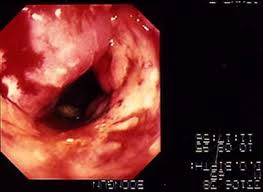

ตัวอย่างภาพติ่งเนื้อในลำใส้ใหญ่และตำแหน่งประมาณนี้(เป็นภาพประกอบจากที่ือื่น)

ลักษณะก้อนเป็นดังนี้ (เป็นภาพประกอบจากที่ือื่น)

และในขณะที่ผมนอนรออยู่นั้นหมอที่ให้ยาผม ได้นำภาพในเคสก่อนหน้าผม และบอกว่าเป็นผู้หญิงอายุ 45 ปี มาเปรียบเทียบให้ผมดู ผมก็พยายามหาติ่งเนื้อแต่ไม่เห็น ผมจึงถามไปว่าไม่เห็นติ่งเนื้อเลยครับ?

หมอก็บอกว่า ให้ดูบริเวณเนื้อผิวของลำใส้ใหญ่ ที่กระจายไปทั่วผิดปกติ ผมจึงถึงบา้งอ้อ. ว่ามันเลยไปจากระยะติ่งเนื้อไปมากแล้วกระจายไปประมาณ 2 ใน 3 ของรอบรู้ลำใส้ใหญ่ตรงส่วนนั้นไปแล้ว ดังภาพตัวอย่าง แต่ยังน้อยกว่านี้มาก

ถ้าประมาณดูในแนวขวาง ก็ได้ประมาณดังภาพตัวอย่างนี้